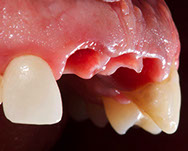

Fig. 12-13-14: Every demanding aesthetic treatment involving implants should have a provisional phase before the definitive prosthesis is delivered. It is mandatory to design natural emergence profiles before finishing the treatment.

7) Managing provisionals in implants in the aesthetic zone. Current concepts.

During the provisional phase of the treatment, a correct and natural emergence profile should be created following the adjacent tooth.

In every emergence profile, two contours can be differentiated (Su 2010):

- Critical contour: The contour is 1 mm immediately below the gingival margin. This contour, when modified, can displace the gingival margin apically.

- Subcritical contour: This is the contour below the critical contour.

When properly managed, this contour can create soft tissue volume (concave); once this volume is created, it can be displaced where needed.